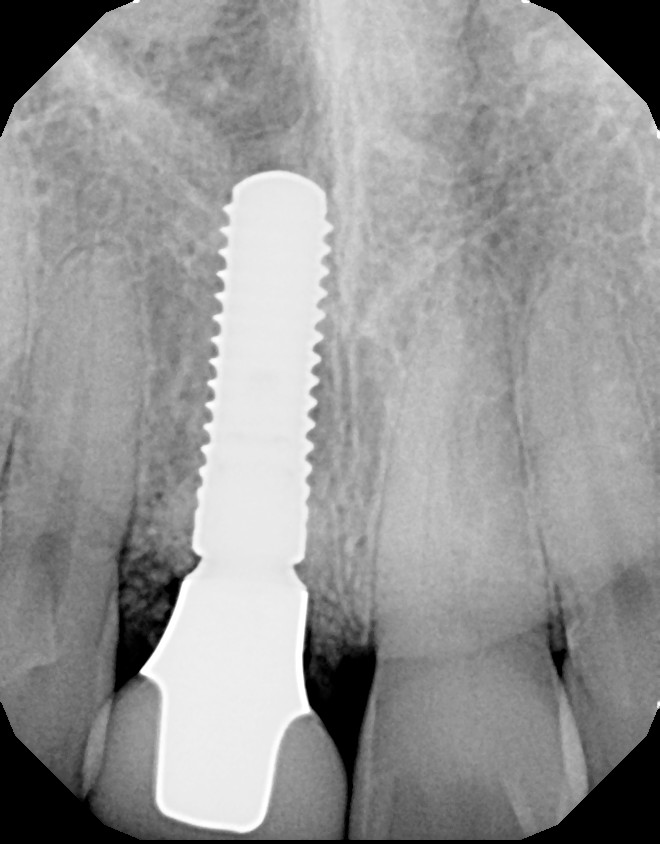

Fig 7. Preoperative radiograph showing previous endodontic therapy on tooth No. 8.

Figure 7

Plugging into digital workflows provides opportunities to integrate CAD/CAM technologies at every step of the treatment process for dental implants. In another example, a patient presented with a failing tooth No. 8 (Figure 6 and Figure 7). After discussing treatment options, the patient chose to forgo any treatment to address tooth and soft-tissue asymmetries and wanted to proceed with a dental implant-supported restoration without additional treatment. After integrated 3-dimensional planning, the tooth was extracted, and then an implant and the final custom CAD/CAM abutment (titanium base with zirconia supra-structure) were placed with a provisional restoration in the same visit (Figure 8 and Figure 9). Soft-tissue grafting was also done at the same visit to address the deficient buccal tissue height on No. 8 (Figure 10). At 3 months, the patient presented for the final restoration, with excellent healing around the implant (Figure 11) and soft-tissue healing guided by the custom abutment (Figure 12).